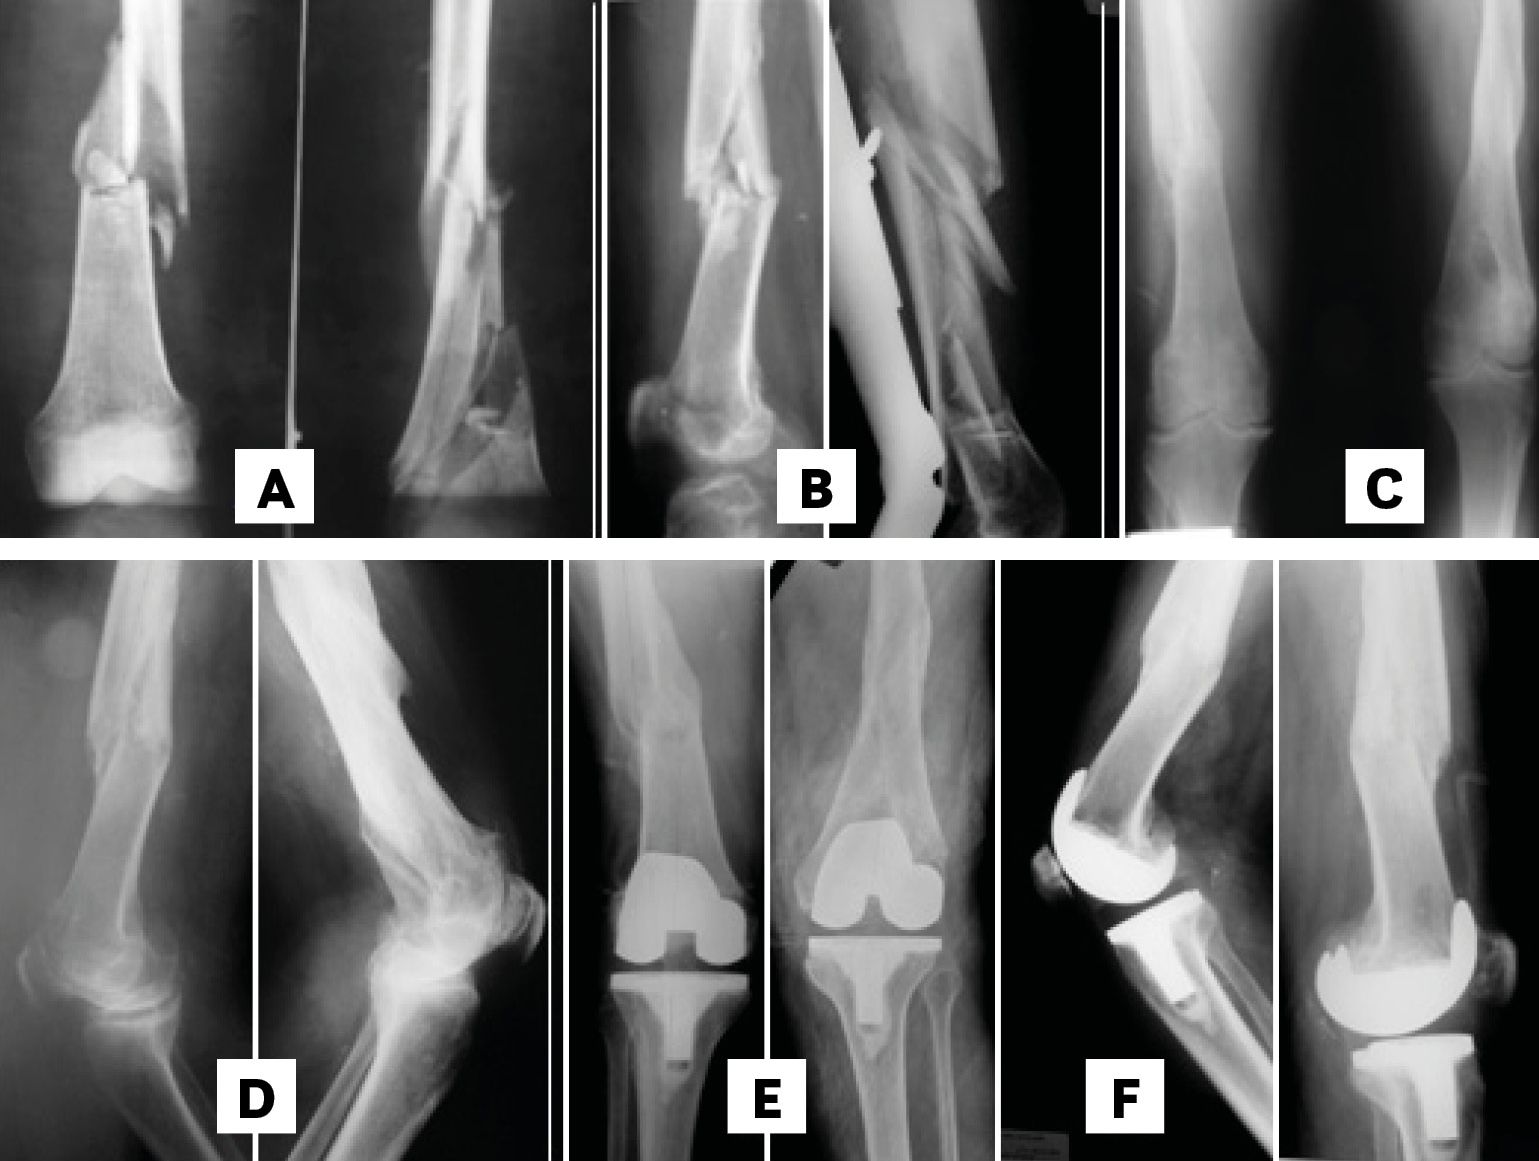

The distal femoral bone cut can be planned using as reference the femoral mechanical axis (cut in 90°) or preferably the axis of the femur proximal to the deformity. The correction of the extra-articular deformity can be made through intra-articular cuts when the femoral distal cut line respects the MCL insertion, since on the lateral side, a lateral epicondylar osteotomy can be performed similar as when dealing with severe valgus deformities. (Figure 5 A & B). [2], Mullaji Arun, Shetty GM Computer-Assisted Total Knee Arthroplasty for arthritis with extra-articular deformity. J. Arthroplasty. 2009;24(8):1164.[3], Panayiotis JP, Karachaloios T, Themistocleous GS Total knee arthroplasty in patients with pre-existing fracture deformity. Orthopedics. 2007;30(5):373.[4], Wolff AM, Hungerford DS, Pepe CL The effect of extraarticular varus and valgus deformity on total knee arthroplasty. Clin Orthop. 1991;271:35-51.[6],Wang JW, Wang CJ Total knee arthroplasty for arthritis of the knee with extra-articular deformity. JBJS Am. 2002;84(10):1769-1774.[8], Mann JW, Insall JN, Scuderi GR Total knee arthroplasty in patients with associated extra-articular angular deformity. Orthop Trans. 1997;21:59.[15] Rand JA, Franco MG Revision considerations for fractures about the knee. In: Goldberg VM (Ed.), Controversies of total knee arthroplasty. Raven Press Ltd, New York, USA, pp. 1991;235-247.

On the femoral side, we prefer an intramedullary guide if it can pass through the angular deformity. If this is not possible, as in deformities in the middle third, we recommend using an extramedullary guide centred on the femoral head, as this can be easily checked with an image intensifier. It is important to understand that for varus femoral deformities near the joint, the entry point for the intramedullary guide can be at the articular surface of the lateral condyle and that this condyle will be the most resected. For valgus deformities, the entrance and the greatest resection will be in the medial condyle.[4], Wolff AM, Hungerford DS, Pepe CL The effect of extraarticular varus and valgus deformity on total knee arthroplasty. Clin Orthop. 1991;271:35-51.[6],Wang JW, Wang CJ Total knee arthroplasty for arthritis of the knee with extra-articular deformity. JBJS Am. 2002;84(10):1769-1774.[18] Cameron HU, Welsh RP Potential complications of total knee replacement following tibial osteotomy. Orthop Rev. 1988;17:39.

The proximal tibial bone resection must be made at 90° to the axis of the tibial shaft distal to the deformity (Figure 5 C & D).[8], Mann JW, Insall JN, Scuderi GR Total knee arthroplasty in patients with associated extra-articular angular deformity. Orthop Trans. 1997;21:59.[2], Mullaji Arun, Shetty GM Computer-Assisted Total Knee Arthroplasty for arthritis with extra-articular deformity. J. Arthroplasty. 2009;24(8):1164.[3], Panayiotis JP, Karachaloios T, Themistocleous GS Total knee arthroplasty in patients with pre-existing fracture deformity. Orthopedics. 2007;30(5):373.[15] Rand JA, Franco MG Revision considerations for fractures about the knee. In: Goldberg VM (Ed.), Controversies of total knee arthroplasty. Raven Press Ltd, New York, USA, pp. 1991;235-247. The use of guides is ruled by the same principles as for the femur.[6]Wang JW, Wang CJ Total knee arthroplasty for arthritis of the knee with extra-articular deformity. JBJS Am. 2002;84(10):1769-1774. A difference is that an “unusual” cut of the tibia generates an asymmetrical gap for the extension and flexion gap equal, which makes these deformities easier to correct through a proper soft tissue release. Nevertheless, there is controversy about the severity of the deformity in which the correction must be performed with an extra-articular osteotomy. [2], Mullaji Arun, Shetty GM Computer-Assisted Total Knee Arthroplasty for arthritis with extra-articular deformity. J. Arthroplasty. 2009;24(8):1164.[3], Panayiotis JP, Karachaloios T, Themistocleous GS Total knee arthroplasty in patients with pre-existing fracture deformity. Orthopedics. 2007;30(5):373.[4], Wolff AM, Hungerford DS, Pepe CL The effect of extraarticular varus and valgus deformity on total knee arthroplasty. Clin Orthop. 1991;271:35-51.[10], Radke S, Radke J Total knee arthroplasty in combination with a one-stage tibial osteotomy. Journal of Arthroplasty. 2002;17(5):533.[11], Windsor RE, Insall JN, Vince KG Technical considerations of total knee arthroplasty after proximal tibial osteotomy. JBJS Am. 1988;70(4):547.[16] Ritter MA, Faris GW Total knee replacement following extra-articular deformities. Orthopedics 2003;26:969.In patients with multiplanar or complex deformities, this possibility is more evident. In case of extra-articular osteotomy combined with TKA in a single stage procedure, the method used to stabilize the osteotomy must be defined. We prefer, if possible, to use femoral or tibial stems instead of plates and screws.